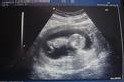

La première échographie

Prescrit entre la 11e et la 13e semaine d'aménorrhée, c'est l'examen qui vous permet de voir votre bébé ! A ce stade on distingue en effet, la tête, les jambes et les bras. Le coeur bat déjà depuis plusieurs semaines. L'échographiste mesure la longueur du foetus, de son fémur, du périmètre de son crâne : il évalue ainsi son âge, et confronte cela avec vos indications sur la date des dernières règles et éventuellement la courbe de température. Vous en ressortez avec vos premières photos et la date de la naissance.